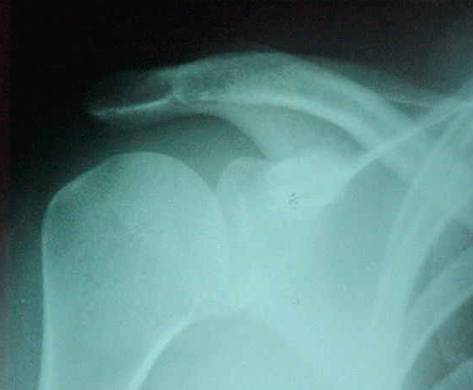

RX No. 3: Rockwood

3 – Rockwood (Avaliação do osteofito sub acromial na avaliação da sindrome de impacto)